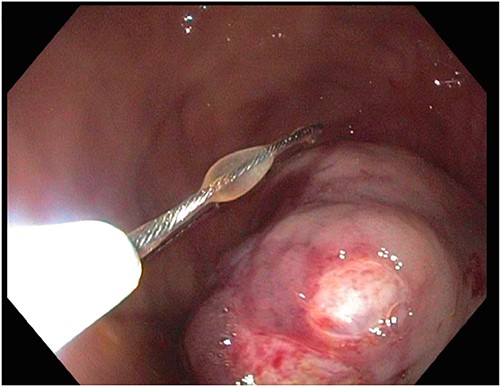

A large fungating gastric mass arising from the body of the stomach on endoscopy.

After a few days, the patient was found to have a large volume of melenic stool. A CT angiogram of the chest, abdomen and pelvis was done, revealing a mass in the antrum and pylorus of the stomach with a portion of the stomach pulled into it, consistent with gastroduodenal intussusception without any active extravasation. Repeat EGD showed a large, fungating, pedunculated mass with no bleeding and no stigmata of recent bleeding in the gastric body (Figs. 3 and4) and confirmed gastroduodenal intussusception. The intussusception spontaneously reduced while attempting to push passed the mass. The mass was too large to resect endoscopically. Given these new findings, the family agreed to surgical intervention. An exploratory laparotomy was made, and the patient underwent partial gastrectomy, distal antrectomy and Billroth II procedure. The resected large gastric body mass within the mid gastric body and two nodes were sent for frozen section and immunohistochemical analysis. The pathology report confirmed the mass as a GIST, spindle cell type with no significant nuclear atypia or mitosis, arising from muscularis propria, without mucosal invasion and R0 margins. The neoplastic cells stained positive for CD117 (KIT), CD34 and Desmin (focally). The tumor was T3N0M0 with a low mitotic rate, histologic grade G1 and was deemed low risk (3.6%). The patient was discharged to a subacute rehab with an uneventful recovery.